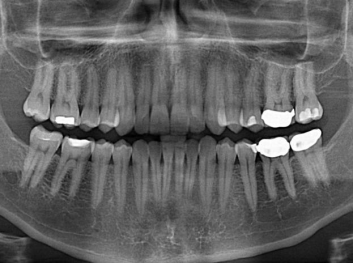

哈佛大學(xué):新型生物材料讓牙齒再生

損壞的牙齒如何自我修復(fù)?近日,來自哈佛大學(xué)和諾丁漢大學(xué)的研究人員研發(fā)了能夠刺激牙齒干細(xì)胞再生的新型生物材料,而這種新材料…